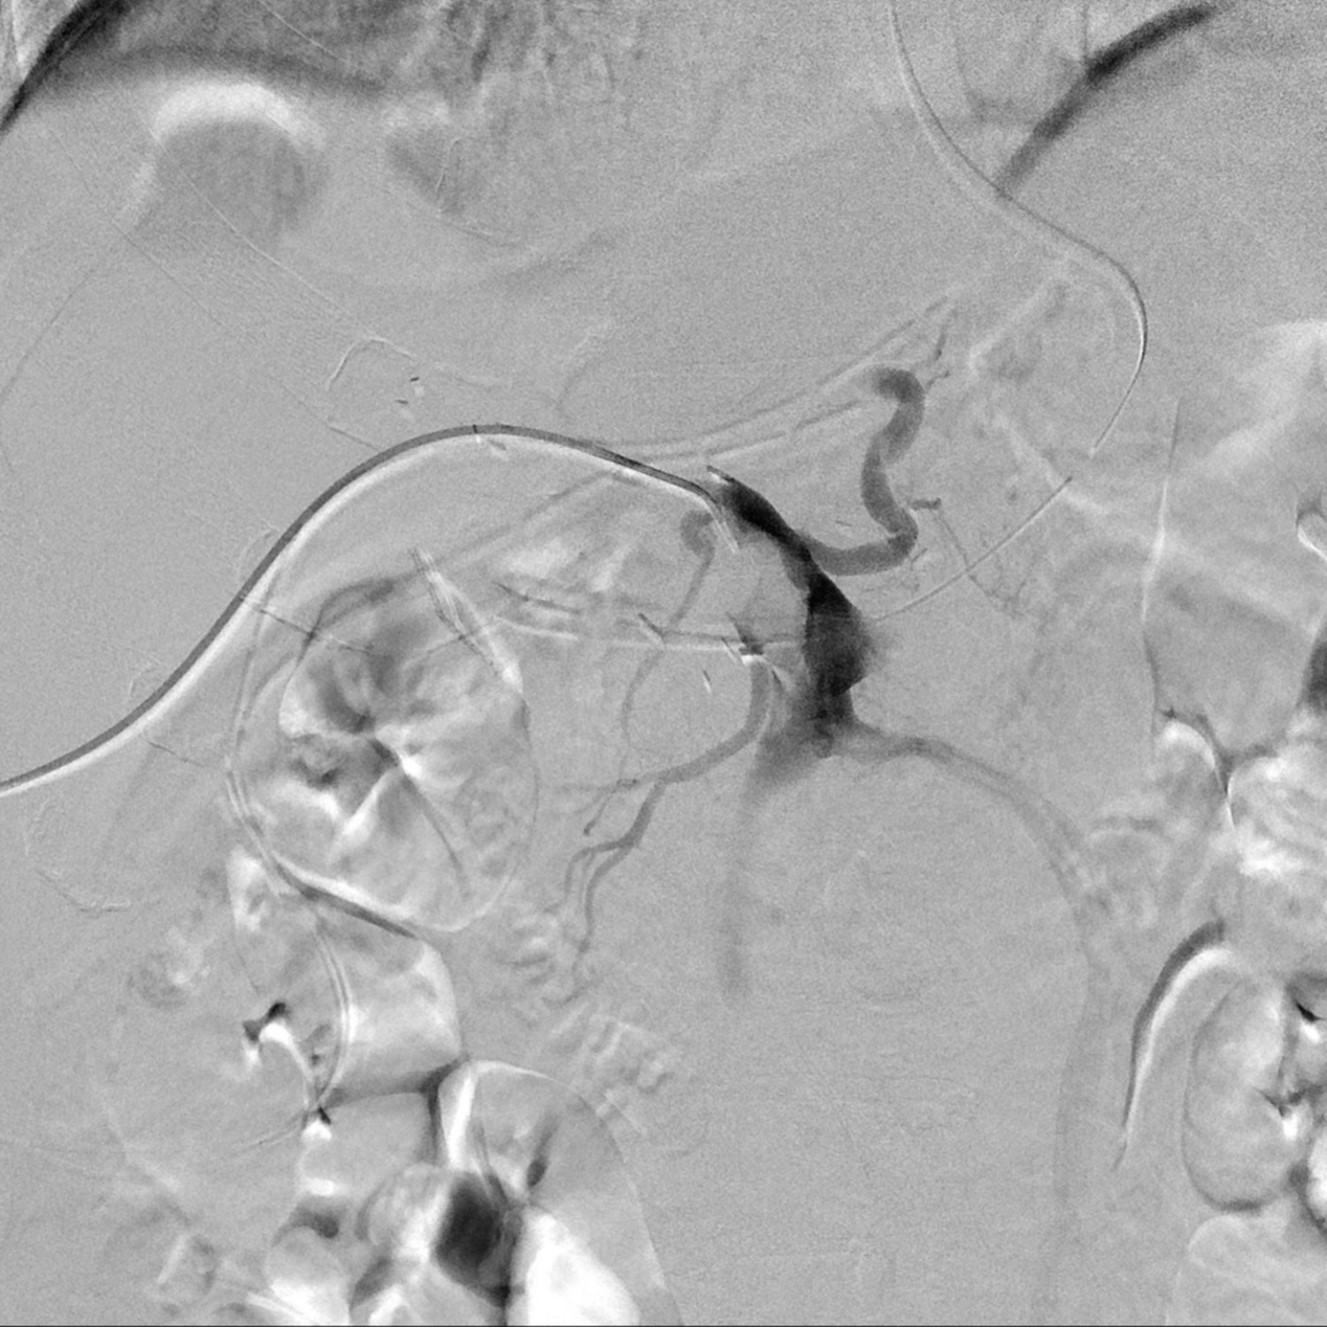

초음파 유도하에 간우엽 S6 담관을 천자하여 5Fr sheath(Terumo, Tokyo, Japan)를 삽입하고 5Fr KMP catheter(Cook, Bloomington, IN, USA)를 상장간막정맥에 위치시키고 시행한 직접 문맥조영술에서 주문맥에 부분적으로 폐쇄가 관찰되었고(Fig. 2a) 혈전으로 인한 폐쇄로 생각이 되었다. 7F McNamara sheath(Cook, Bloomington, IN, USA)를 삽입하여 흡인 혈전제거술을 수차례 시행하여 소량의 혈전이 흡인되었으나 문맥 혈류는 여전히 막혀있었음. 이에 12mm balloon(EverCross, EV3, Plymouth, MN, USA)으로 경피혈관확장술을 시행하였으나 이후 시행한 문맥조영술에서도 문맥 폐쇄 소견은 여전히 보였음. 이어 주문맥에 14x40mm 자가팽창형금속 스텐트(ELuminexx, Bard, Tempe, AZ, USA)를 설치하였으나 문맥에 폐쇄된 분절을 전부 포함할 수 없어 근위부에 12x4cm의 자가팽창형금속 스텐트(Zilver, Cook, Bloomington, IN, USA)를 추가로 설치하고 이후 12mm balloon으로 혈관확장술을 시행하였음. 마지막으로 시행한 문맥조영술에서 문맥은 개통되어 혈류는 회복되었으나 문맥 원위부에는 혈전이 일부 남아있었음(Fig. 2b). 천자한 통로는 histoacryl로 색전후 시술을 종료하였음. 간문맥 스텐트 설치 후 5일 뒤 시행한 CT에서 문맥 스텐트는 개통되어 있었고 조영 후 사진에서 문맥 혈류가 말초까지 가는 것을 확인할 수 있었음(Fig. 3). 환자는 이후 간기능 부전 및 문맥 고혈압의 증상 및 소견 없이 회복하여 퇴원하여 외래 추적 관찰 중임.

Fig. 2. A

Figure 2. Portogram before the stent insertion (A) shows segmental obstruction in main portal vein and filling defect probably due to the thrombus. Portogram after portal vein stent demonstrates the patent stent and portal flow (B).